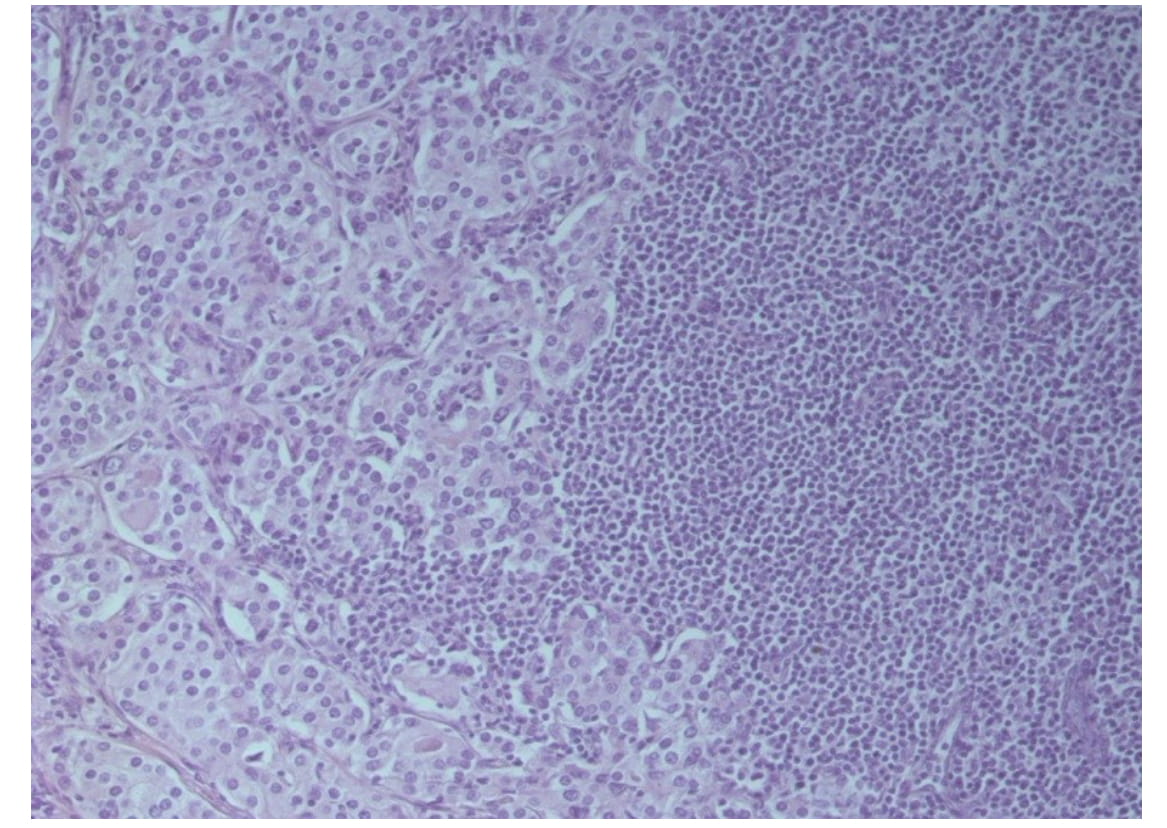

During follow-up examination, in 16 patients (18.8%) hematogenic metastases were revealed: in 13 patients (15.3% of the total patients included into the research) – isolated damage to the spine and skeletal bones, in 3 patients (3.5%) – metastatic foci in visceral organs. Morphological examination of preparations of the regional lymph node tissue showed existence of metastases in 30 patients (35.5%, Fig. 2).

Fig. 2. A metastasis of acinaradenocarcinoma into a regional lymph node. Staining with hematoxylin and eosin, x200